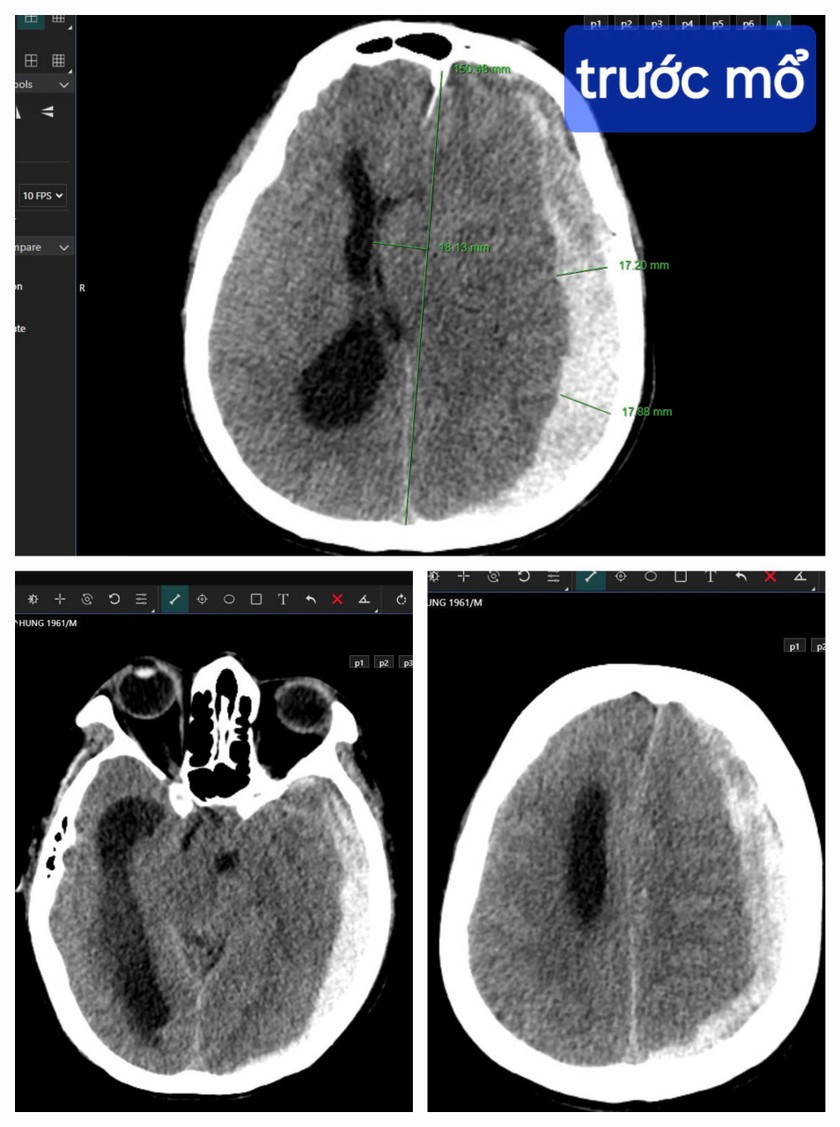

Kết quả chụp CT cho thấy bệnh nhân bị tụ máu dưới màng cứng bán cầu não trái, thoát vị qua liềm đại não sang phải. |

Trong tình huống khẩn cấp này, sự sống của bệnh nhân rất mong manh, bị tụ máu dưới màng cứng bán cầu não trái, thoát vị qua liềm đại não sang phải, bác sĩ phải chạy đua cùng thời gian, giành lại sự sống cho bệnh nhân từ tay “tử thần”.